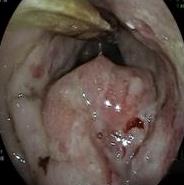

• 耳内镜下软骨-软骨膜复合体用于慢性化脓性中耳炎合并耳真菌病鼓室成形术的疗效分析

2026, 32(1):55-61. DOI: 10.12235/E20240777

摘要 (44) HTML (13) PDF 2.20 M (55) 评论 (0) 收藏

摘要:目的 探讨慢性化脓性中耳炎合并耳真菌病患者行耳内镜下软骨-软骨膜复合体鼓室成形术的临床疗效。方法 选取2021年1月-2023年12月该院收治的,于耳内镜下采用耳屏软骨-软骨膜复合体行鼓室成形术的慢性化脓性中耳炎患者68例,根据是否合并过耳真菌病,将患者分为真菌组和对照组,各34例。真菌组术前合并耳真菌病,均行抗真菌治疗后好转,其中18例合并湿耳;对照组未曾合并过耳真菌病,术前均为干耳。所有患者均接受了耳内镜下鼓室成形术,采用软骨-软骨膜复合体修复穿孔。术后随访至少3个月。于术前和术后3个月,检查纯音听力。观察两组患者鼓膜修补成功率、听力改善情况和干耳时间。结果 真菌组和对照组的鼓膜修补成功率分别为88.24%(30/34)和91.18%(31/34),差异无统计学意义(P > 0.05);两组患者术后3个月气骨导间距明显小于术前,差异有统计学意义(P < 0.05);但两组间比较,差异无统计学意义(P > 0.05);真菌组干耳时间长于对照组,差异有统计学意义(P < 0.05)。结论 慢性化脓性中耳炎合并耳真菌病有时伴有湿耳,患者需要更长的时间来达到完全健康的状态,使用软骨-软骨膜复合体的耳内镜下鼓室成形术,是治疗慢性化脓性中耳炎合并耳真菌病患者的有效方法。值得应用于临床。